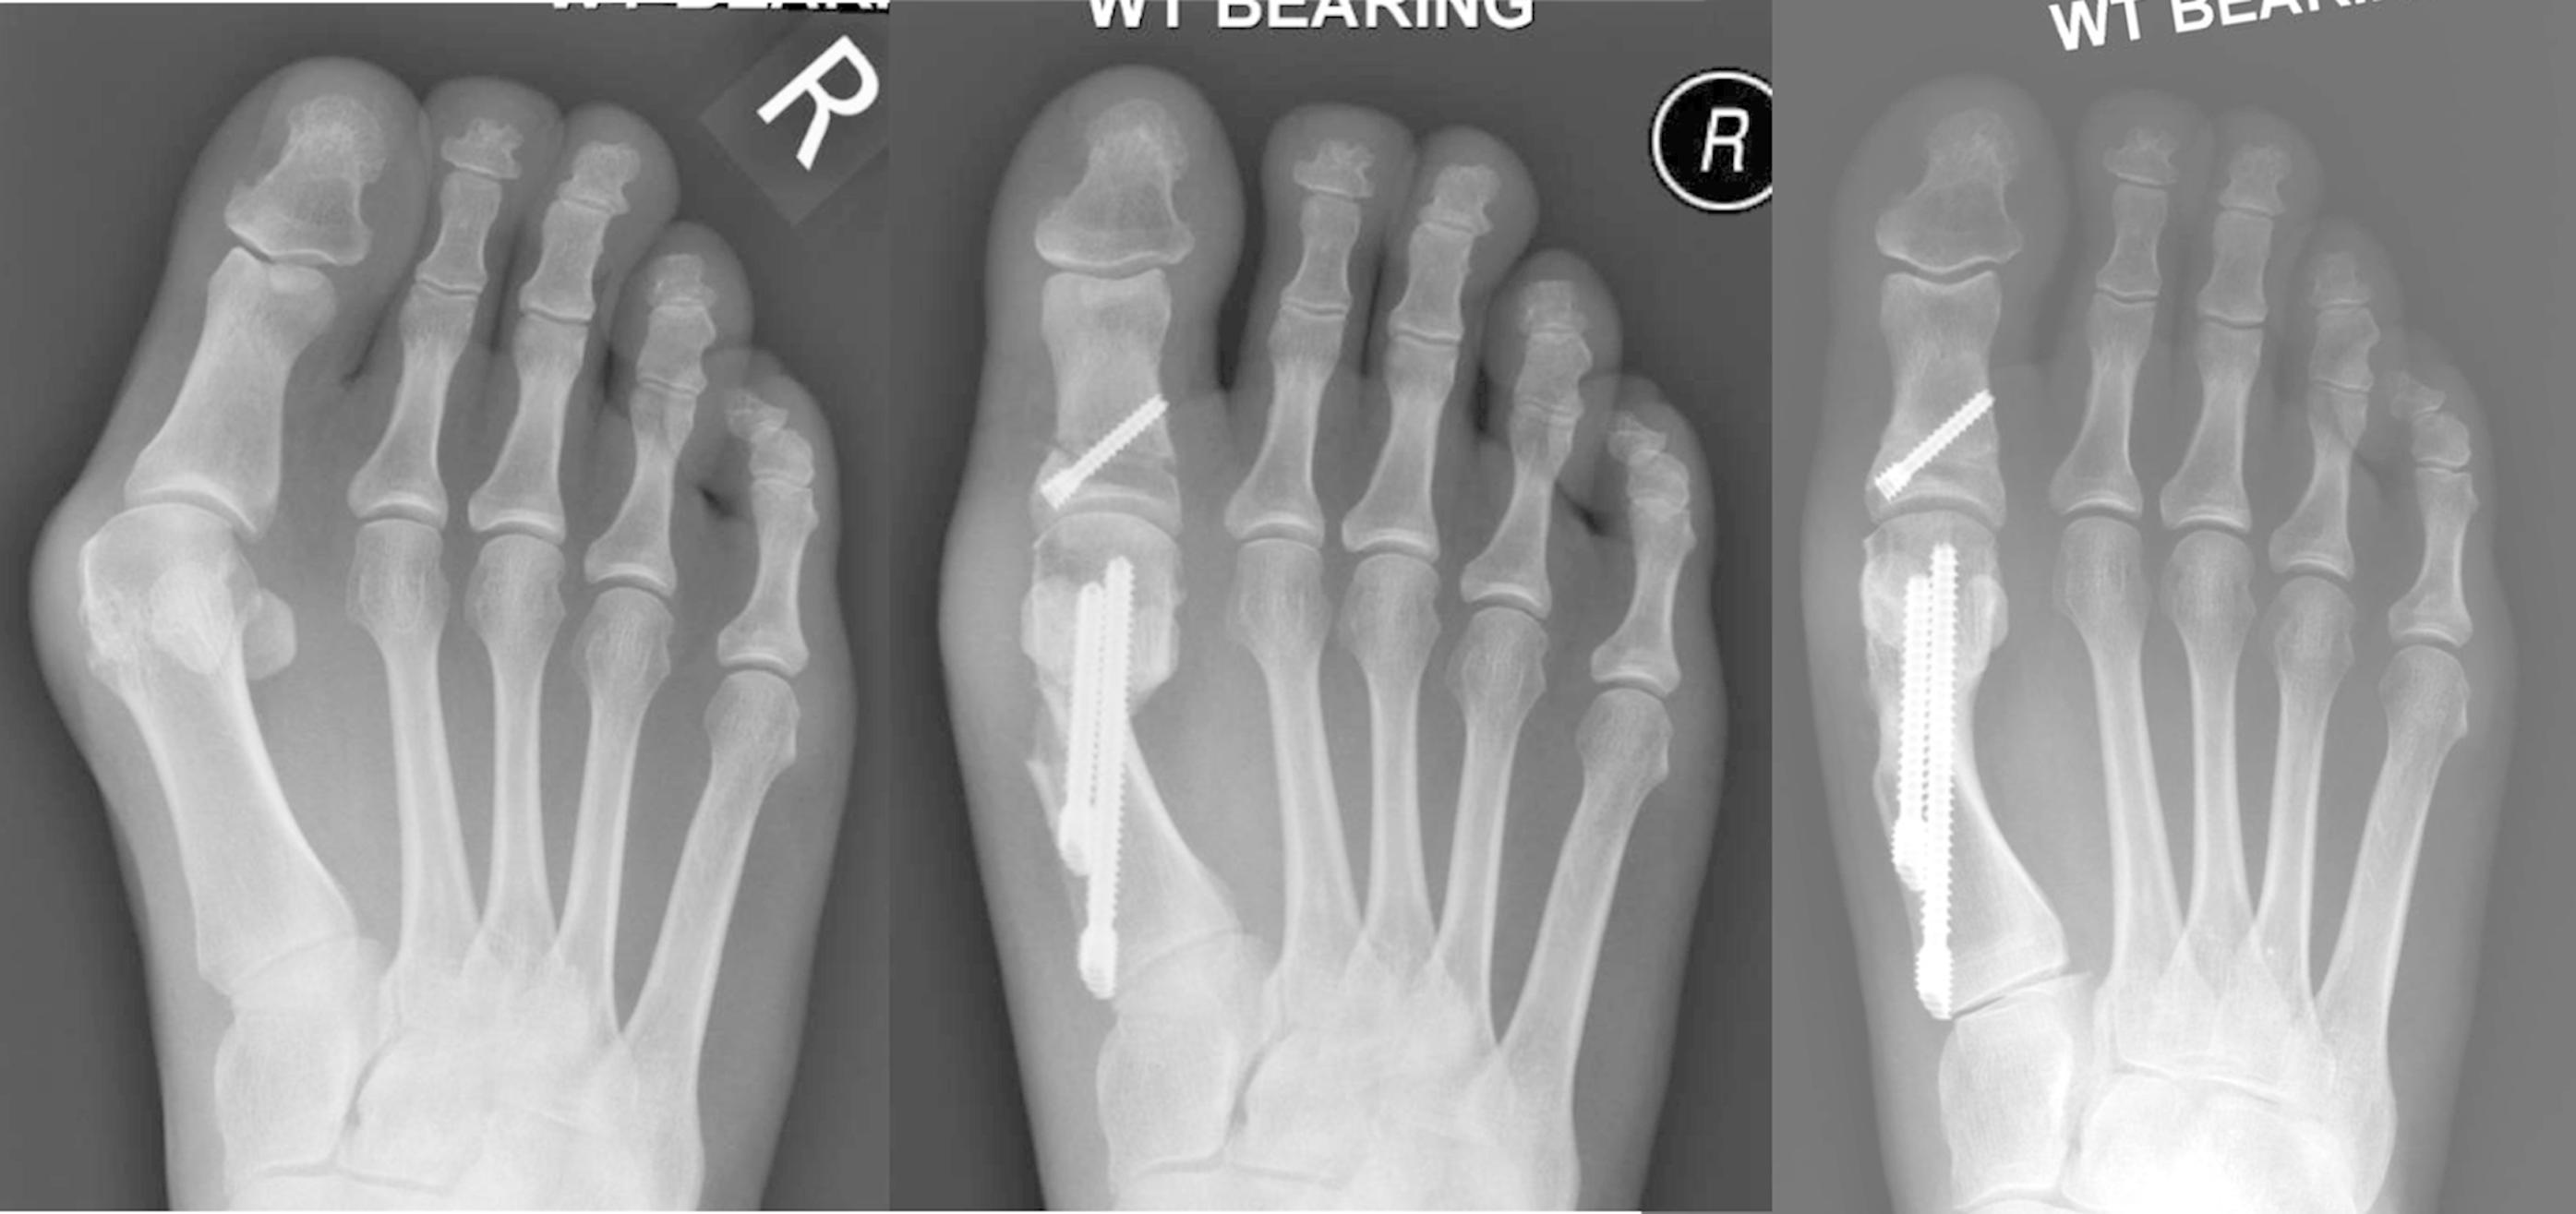

Вальгусная деформация пальца мкб 111 фотографий